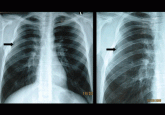

ArticleBony bridge of a bifid ribAuthor:Gaye UlubayPublish date: April 1, 2010A 21-year-old man presents with 3 days of cough and hemoptysis. A chest x-ray reveals a congenital anomaly.Read More